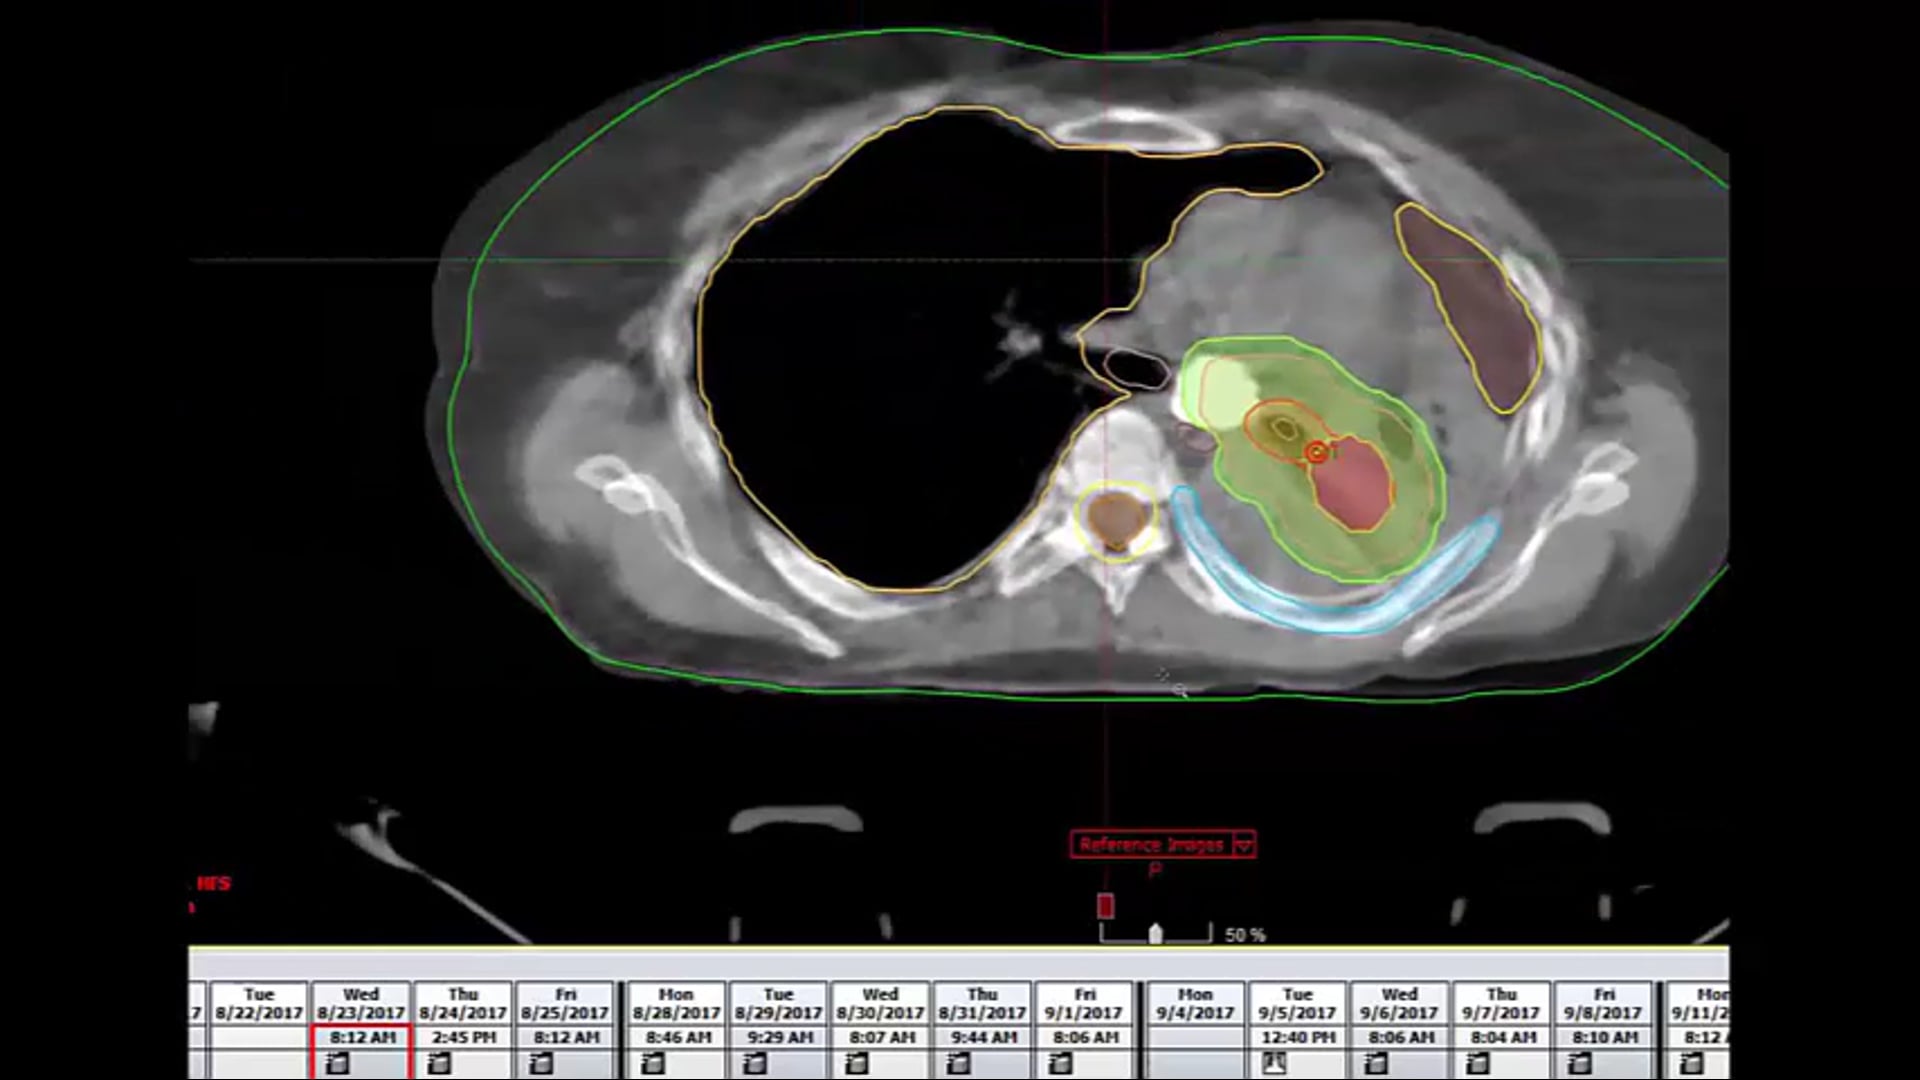

refused chemotherapy, tumor, dose-volume constraints, CORSAIR, 55Gy 20 regimen, SBRT, CTV, clinical target volume, fractionation